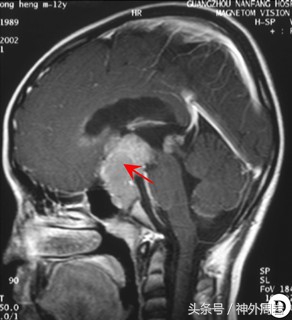

头颅核磁:鞍区巨大肿瘤,向上生长达三脑室及其后部、侧脑室、双侧海绵窦。肿瘤最大直径为9.3cm。

照片来自网络